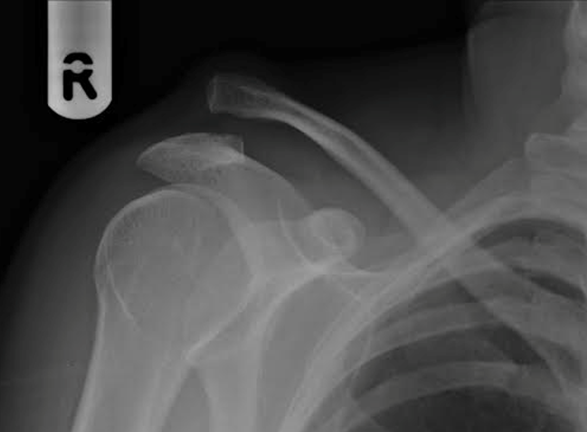

With direct force, normally a fall onto the tip of the shoulder, the joint can be injured and become painful and unstable.   In some cases this pain and/or instability requires surgery. The x-ray below shows a high-grade dislocation of the AC joint.